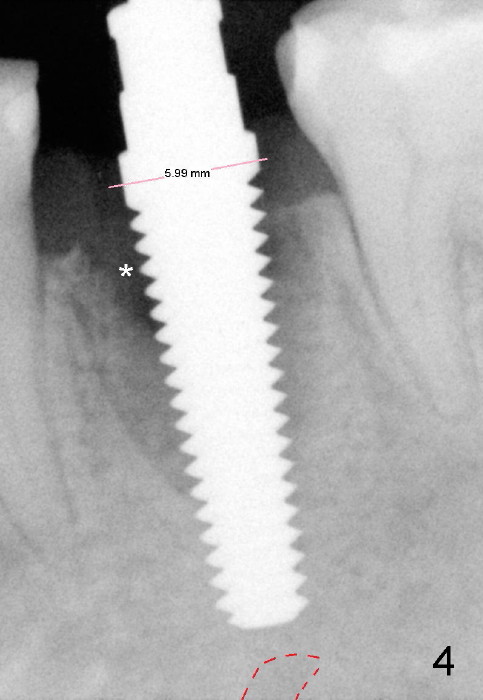

To avoid injury to the mental loop (Fig.2 dashed line), the depth of initial osteotomy is tightly controlled apical to the bottom of the socke. Accurate measuring is the 2nd important measure to assure no or minimal neurological trauma. The wide socket (due to infection) allows to place an implant as wide as 7 mm.

Taking multiple intraop X-ray is also necessary for depth adjustment (Fig.3-5). For example, when a 5x20 mm tap is inserted at the depth of 17 mm, it is close to the mental loop (Fig.4), whereas the binding to the bone is minimal. So a larger implant is to be placed at a shallower depth (Fig.5: 6x17 mm with insertion torque >60 Ncm). The shallower implant placement creates limited space for future abutment and crown (Fig.6,7). A short abutment will be used and the implant margin will be prepared as low as possible. As expected, the wound heals in a week (Fig.8).